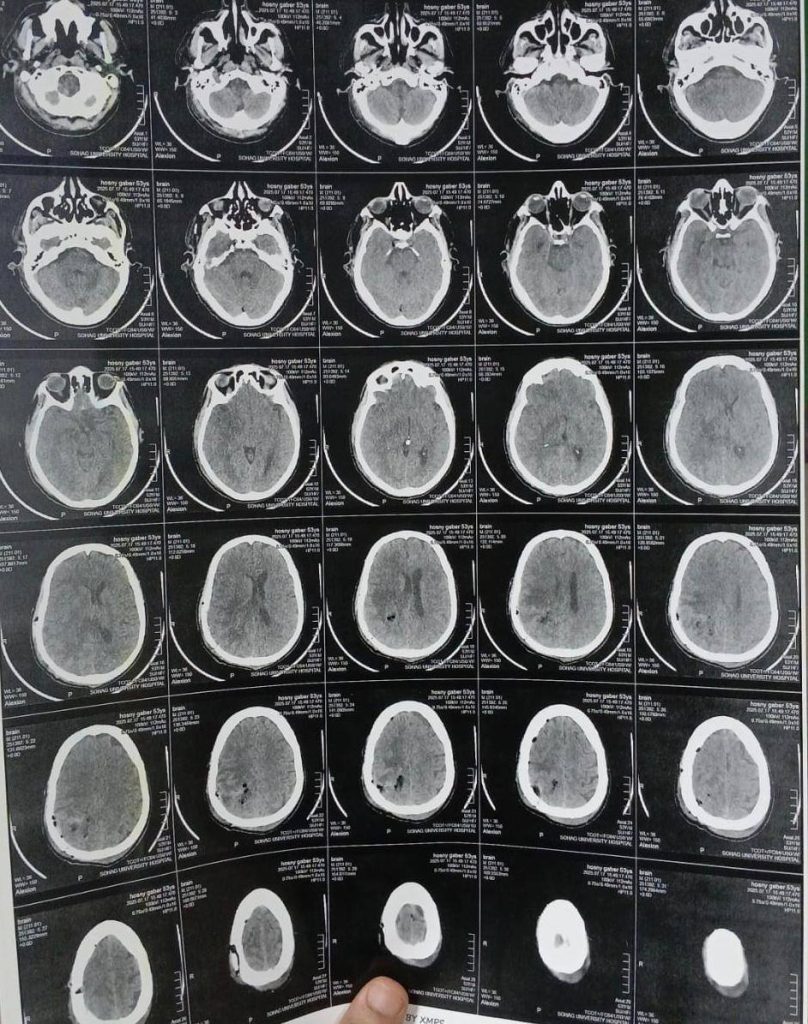

ومن جانبه، أوضح الدكتور مجدي القاضي، عميد كلية الطب البشري ورئيس مجلس ادارة المستشفيات الجامعية، أن المريض كان يعاني من اضطراب بدرجة الوعي وشلل نصفي بالجانب الأيسر، وتبين من الفحوصات وجود ورم بالمخ بحجم ٧×٥×٤ سم، وقد تم استئصاله بالكامل خلال جراحة استغرقت ٤ ساعات، مشيرًا إلى أن الفريق الجراحي استخدم تقنية حديثة تعتمد على حقن الصبغات الورمية لتحديد حدود الورم بدقة.

وأشار الدكتور أحمد كمال عبدالحميد، المدير التنفيذي للمستشفيات الجامعية واستاذ جراحة المخ والأعصاب والعمود الفقري، والذي أجرى الجراحة، إلى أن العملية تمت بإستخدام ميكروسكوب جراحي متطور، والحفار الكهربائي لفتح عظام الجمجمة، مما ساهم في الوصول الآمن إلى الورم واستئصاله بالكامل دون التأثير على الأنسجة الحيوية. مضيفًا أن المريض استعاد وعيه بالكامل بعد الجراحة، وعادت حركة الأطراف إلى طبيعتها.